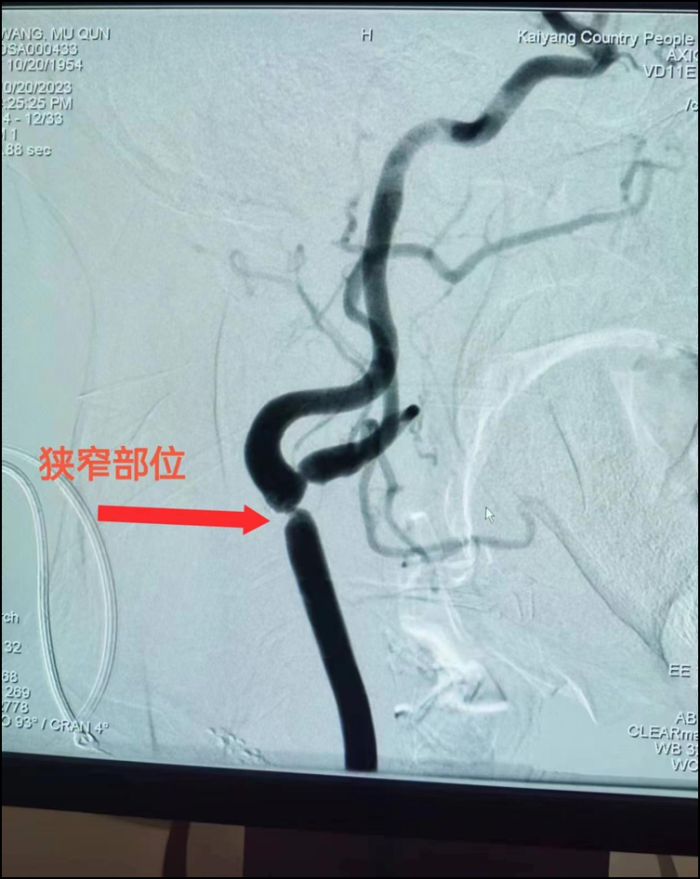

患者汪某,女,69岁。患者因"突发头晕1+天"入住开阳县人民医院神经内科。入院后完善CTA检查,报告:左侧颈总动脉分叉部混合性斑块,局部管腔中度狭窄;左侧颈内动脉C7段局部似见一小结节状突起,动脉瘤待排,必要时DSA进一步检查。后与家属沟通同意后行全脑血管造影示:左侧颈总动脉近分叉处重度狭窄约75%。经综合评估患者远期卒中风险高,经与家属充分沟通告知病情后,病人及家属同意行介入手术治疗,术前完善相关检查无明显手术禁忌症,择期手术。

术前血管显影

手术顺利,术中患者生命征平稳,支架植入后造影见原狭窄处明显改善,患者原狭窄处发生闭塞风险降低,术后继续服用阿司匹林肠溶片、硫酸氢氯吡格雷片、阿托伐他汀钙片治疗,头昏症状明显改善出院。